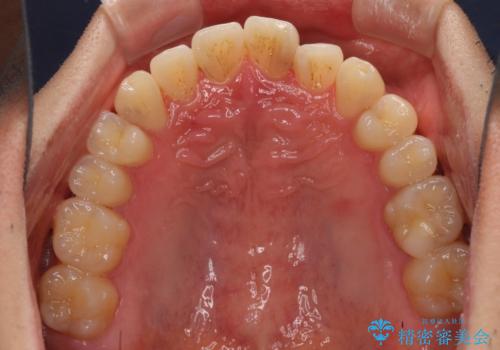

気になる前歯のデコボコをインビザラインで解消

- 前歯のデコボコを気にして来院された患者様です。

主に下顎歯列全体の後方移動とIPR(歯と歯の間を削る)によってデコボコが解消するように設計し、インビザラインにより治療を行うこととしました。

インビザライン矯正特有の、治療後半で前歯のみが強く接触する症状が発現し、咬み合わせ改善に期間を要することとなりました。